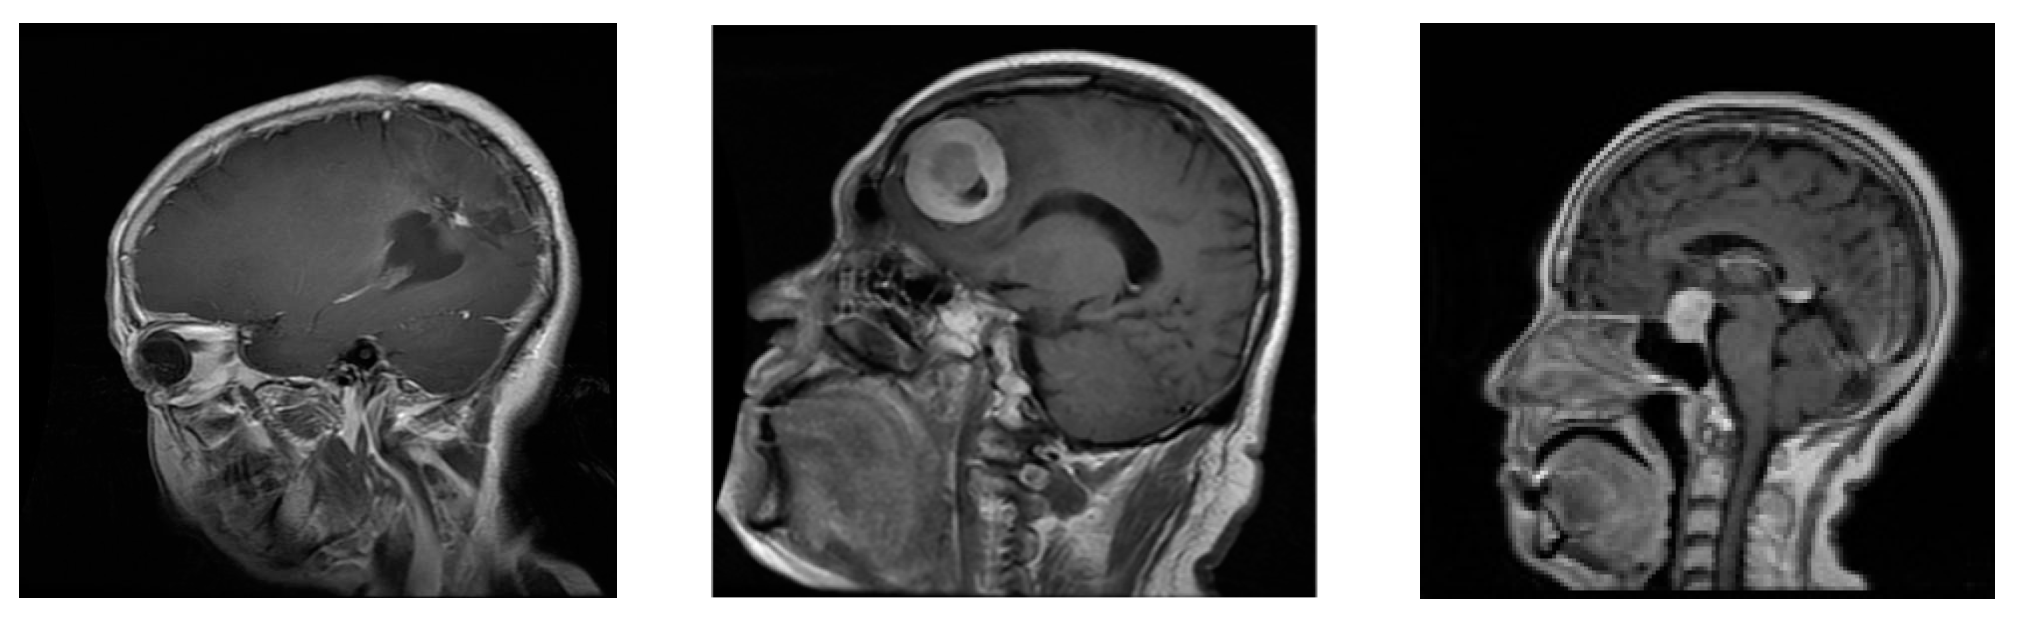

Burak [17] effectively utilized GradCAM to detect tumor areas in MRI scans from their database, producing informative heat maps that accurately highlighted the regions of interest (tumors). With this technique, we were able to visualize and try to understand which specific parts of the images are crucial for the accurate classification performed by the CNN that achieved the best results in our project. By using GradCAM, we generated heatmaps that highlighted the regions in the images that had the most influence on the classification decision. To explore the regions of interest in each tumor category, we applied the GradCAM technique to three representative images of each tumor type in our dataset. The results revealed the specific regions in each image that influenced the final classification made by the neural network. In Figure 3, Alex Net’s GradCAM analysis revealed its focus on specific regions, notably the skull and tumors, vital for accurate tumor classification. The highlighted areas, depicted in intense red tones, offer key visual cues for tumor identification. This correlation between tumor position relative to the skull and CNN’s classification implies significance in tumor type classification.

Figure 3. RMI’s image heat map for a (a) glioma, (b) meningioma, and (c) pituitary.